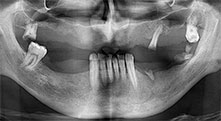

dentatura residua

Un paziente di 40 anni con una dentatura residua limitata desiderava un restauro basato su impianto. Dal momento che è un fumatore, era controindicato un rialzo del seno mascellare con una protesi fissa. È stata quindi programmata una protesi a barre.

impianti

I quattro impianti sono fissati come programmato. I molari mascellari distali possono comunque essere utilizzati per fissare la protesi in linea introdotta un mese dopo l'impianto.